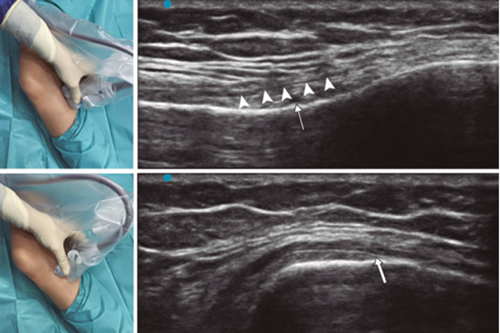

Ultrasound-guided genicular nerve radiofrequency

Fig. 3. Sonoanatomy and technique for performing superior medial genicular nerve block (SMGN). The transducer is located on the distal long axis of the femur and once the position of the SMGN (asterisks) is known, the probe is rotated 90 degrees to obtain a view of the femur short-axis (don't forget to keep the same depth that we find the SMGN on the long axis). VM (vastus medialis).

Fig. 4. Sonoanatomy and technique for performing inferior medial genicular nerve block (IMGN). The transducer is located on the proximal long axis of the tibia and we identify the vasculonervious package of the IMGN (arrow) just below medial collateral ligament (arrowheads). Then the probe is rotated 90 degrees to obtain a short-axis view of the tibia (don't forget to keep the same depth as the IMGN found on the long axis).

After performing knee asepsis/antisepsis, surgical field placement, and the sterile sheath of the high frequency linear transducer, we proceed to locate the SMGN (Figure 3). Placing the probe in a coronal plane on the inner face of the knee, we slide it cranially to visualize the junction of the metaphysis to the femoral diaphysis and the superior medial genicular artery/nerve (ASMGN), usually located near the periostium of the femur (if this neurovascular structure is not found, the junction between metaphysis and femoral diaphysis is taken as a reference). The mid-point of the transducer corresponding to ASMGN is then marked on the skin and the transducer is rotated to be placed in the transverse or axial plane to view ASMGN on the short axis (if this structure is not visible, confirm that we are at 50 % depth of the femur). In this cross-section the needle of the TRF is advanced in plane from anterior to posterior toward the ASMGN or to a depth of 50 % of the thickness of the femur. Finally, the transducer is rotated 90° again, leaving it in a coronal plane to check that the needle tip is near the ASMGN or the junction of the metaphysis and femoral diaphysis (14,16,19).

To locate the IMGN (Figure 4), we placed the transducer in a coronal plane on the inner face of the knee, sliding it caudally to identify the diaphysis junction with the tibial metaphysis and the inferomedial genicular artery/nerve (AIMGN). And we repeat the same steps we used for SMGN. If the AIMGN is not found, the reference to be taken shall be the depth of 50 % of the thickness of the tibia (14,16,19).

To locate the SLGN, the patient must be supine with the lower limb in internal rotation, obtaining good exposure to the lateral side of the thigh. We place the linear transducer in a coronal plane on the lateral side of the knee, slide it in a cranial direction to visualize the junction of the metaphysis with the femoral diaphysis and the superior lateral genicular artery/nerve (ASLGN), and repeat the same steps that we use for SMGN (14,16,19).

Then we found that the threshold of sensory stimulation at 50 Hz that triggers a paresthesia or pain is less than 0.6 V, and to avoid motor nerve damage there should be no fasciculations of the lower limb with a motor stimulus at 2 Hz with 2.0 V. If everything is correct, we administered 2 ml of lidocaine 2 % or mepivacaine 2 % in each nerve and performed the TRF at 80 °C for 90 seconds (9,14).

In our review we find other anatomical landmarks that can help us locate the genicular nerves. Yasar et al. (20) identified that the SMGN is located one centimeter before the adductor tubercle, the IMGN is located at the midpoint between the peak of the medial tibial epicondyle and the beginning of the insertion of the medial collateral ligament fibers over the tibia.